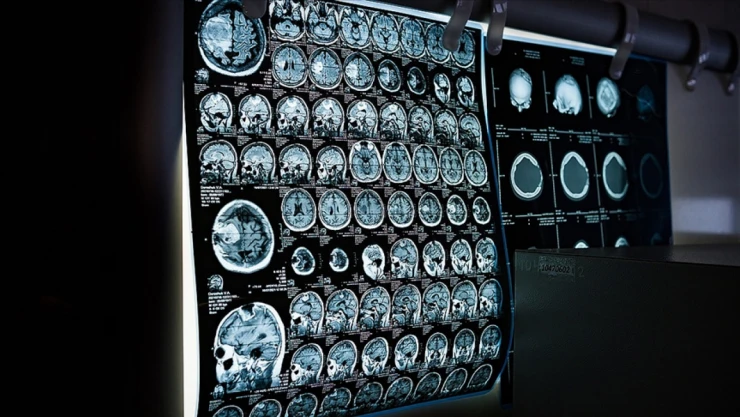

- Türkiye'de Geçen Yıl 9,5 Milyon Kanser Taraması Yapıldı

Türkiye'de Geçen Yıl 9,5 Milyon Kanser Taraması Yapıldı

Sağlık Bakanlığınca yürütülen toplum tabanlı kanser taramaları kapsamında 3 milyon 300 bin meme kanseri, 3 milyon 500 bin rahim ağzı kanseri, 2 milyon 700 bin kolon kanseri taraması gerçekleştirildi.

Sağlık Bakanlığınca yürütülen Türkiye genelindeki toplum tabanlı kanser taramaları kapsamında, geçen yıl 9 milyon 500 bin tarama yapıldı.